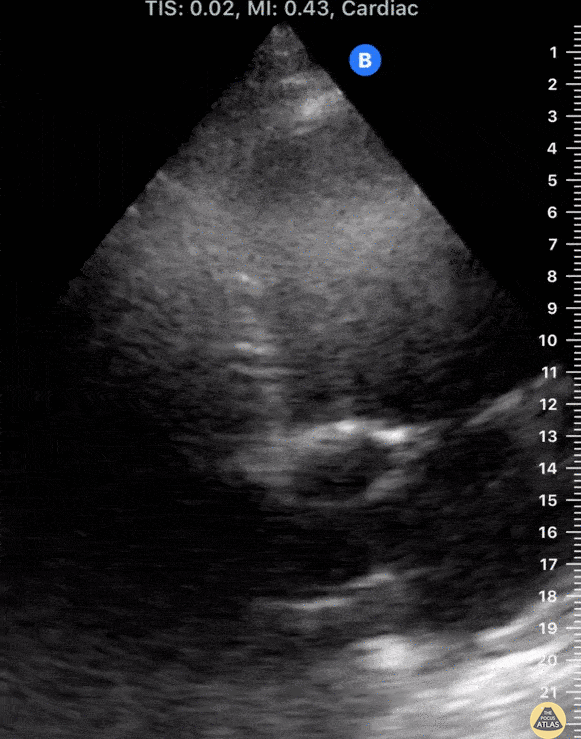

24-yo-male who had been diagnosed with granulomatosis with polyangiitis 10 months prior presented with DOE and progressive bilateral lower extremity edema. Clinical suspicion of cardiac dysfunction was confirmed by POCUS; seen here is the apical 5-chamber view, nearly unable to fit on screen due to severity of bi-ventricular dilation and impaired systolic function. Tessa W. Damm, DO Intensivist, Critical Care Medicine & Neurocritical Care. Wisconsin, USA @DrDamm